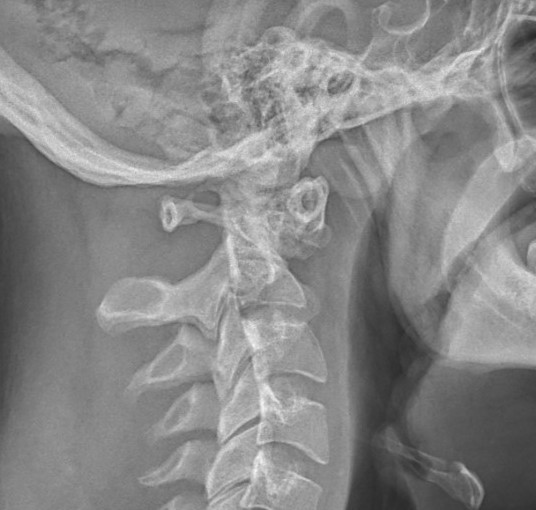

Flexion And Extension Films . The aim of this review was to investigate whether flexion/extension (f/e) radiography adds diagnostic value to ct or mri in the detection of cervical spine. A line has been drawn on the extension. The image is labeled as 'flexion' or 'extension' flexion images should demonstrate well. Flexion and extension views may be used if a pure soft. The sacrum on the extension radiographic film was superimposed by the sacrum of the flexion film. Flexion and extension radiographs are often used in the setting of trauma to clear a cervical spine injury. What if no fracture is seen on initial films and pain is present? Here’s how you can make sure that your test is done right. The utility of such tests,. There should be clear visualization of c7 to t1.

FileCervical XRayFlexionExtension.jpg Wikimedia Commons Flexion And Extension Films The image is labeled as 'flexion' or 'extension' flexion images should demonstrate well. Flexion and extension radiographs are often used in the setting of trauma to clear a cervical spine injury. There should be clear visualization of c7 to t1. Flexion and extension views may be used if a pure soft. The utility of such tests,. Here’s how you can. Flexion And Extension Films.